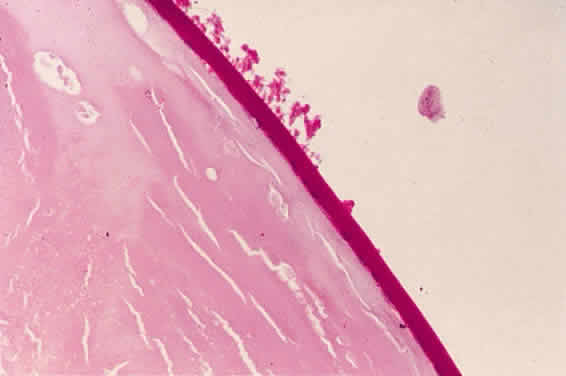

Accumulation of exfoliative material may be detected histopathologically throughout the anterior segment to include the lens, iris, trabecular structures, conjunctiva, ciliary body, and zonules. The deposition of fibrillar eosinophilic material on the anterior lens capsule is the classic histopathologic feature of XFS (Fig. 9). Ultrastructural studies also indicate some degree of actual exfoliative changes or peeling of the anterior lens capsule74 (Figs. 10 and 11). In addition, Ashton and associates describe a degenerative band containing exfoliative material within the inner half of the lens capsule.5 Bertelsen and coworkers independently noted projection of coarse fibrils from the lens surface into the deep portion of the lens capsule to form an amorphous layer of the lens capsule between the lens epithelium and normal lens capsule.6 Thus, studies indicate that exfoliative material accumulates on the anterior lens surface but also that the lens capsule itself may be involved, and that the underlying epithelial layer may at least partially contribute to the production of the exfoliative material.

A ground glass-appearing precapsular layer sometimes is observed on the anterior lens capsule of elderly patients. Ultrastructural studies show this layer to have a fibrillar structure similar to exfoliative material, indicating that this may be a precursor to the XFS.75,76

Exfoliative material consists of an irregular meshwork of fibers composed of fibrillar subunits.74,92 Masses of these fibers correspond to the material seen clinically (see Fig. 10). The individual fibrils, which measure 6 to 8 nm in diameter and exhibit cross-banding at 10- to 12-nm intervals, are hypothesized to consist of macromolecules with a protein backbone and polysaccharide side chains.93–95 In contrast to collagen, the amino acid content of exfoliative material lacks hydroxyproline.96 Ringvold and Husby noted histochemical, immunologic, and ultrastructural features that led them to classify exfoliative material as an amyloid-like substance.97 Repo and associates note Congo red-positive staining for amyloid in the vessel walls of 7 of 13 iris specimens from exfoliation patients and believe that these findings support the theory that XFS is associated with amyloid.59 Immunohistochemical studies by other investigators show heparin sulfate and chondroitin sulfate proteoglycans, laminin, entactin/nidogen, fibronectin, and amyloid P protein to be components of exfoliation material.98,99 Schlötzer-Schrehardt and coworkers suggest that the material may be an expression of a disordered extracellular matrix synthesis.98